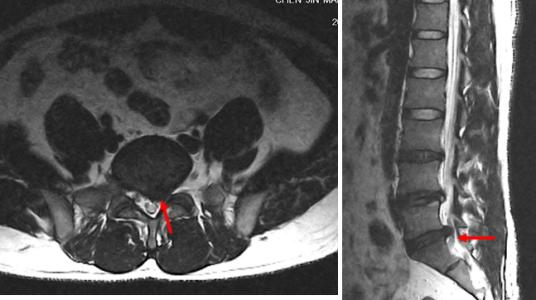

图源:作者提供

2、腰椎间盘 CT 和腰椎 MRI

显示突出的髓核、硬膜囊和神经根受压等情况。